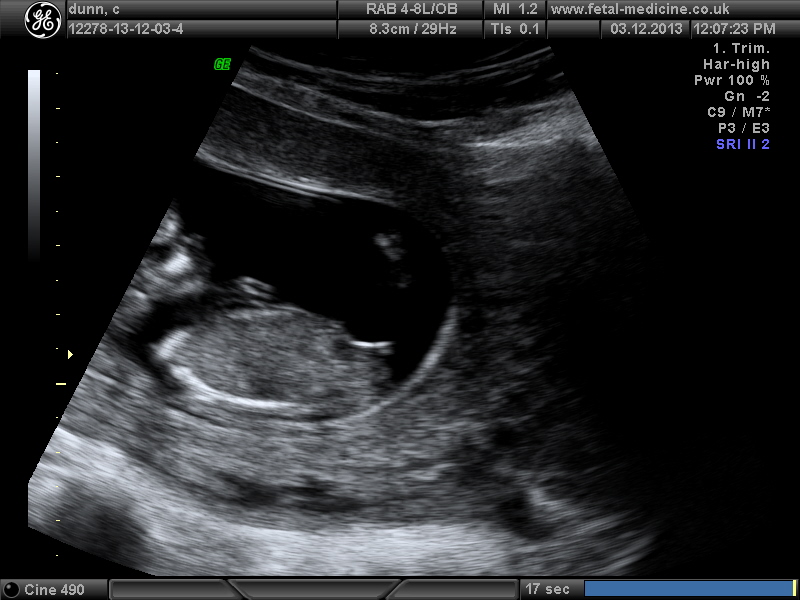

hello, please have a guess boy or girl, thankyou scan was 12+1 day.

i am very sure i see girl nub...but just my opinion though....but i am sure....